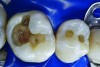

Figure 6. Amalgam is not usually bonded to the walls of the cavity preparation; thus, a space of several microns commonly exists between the restoration and the prepared surfaces. This leads to a potential for microbial invasion and secondary caries, as in this case of these defective amalgam restorations with recurrent decay.

Figure 6